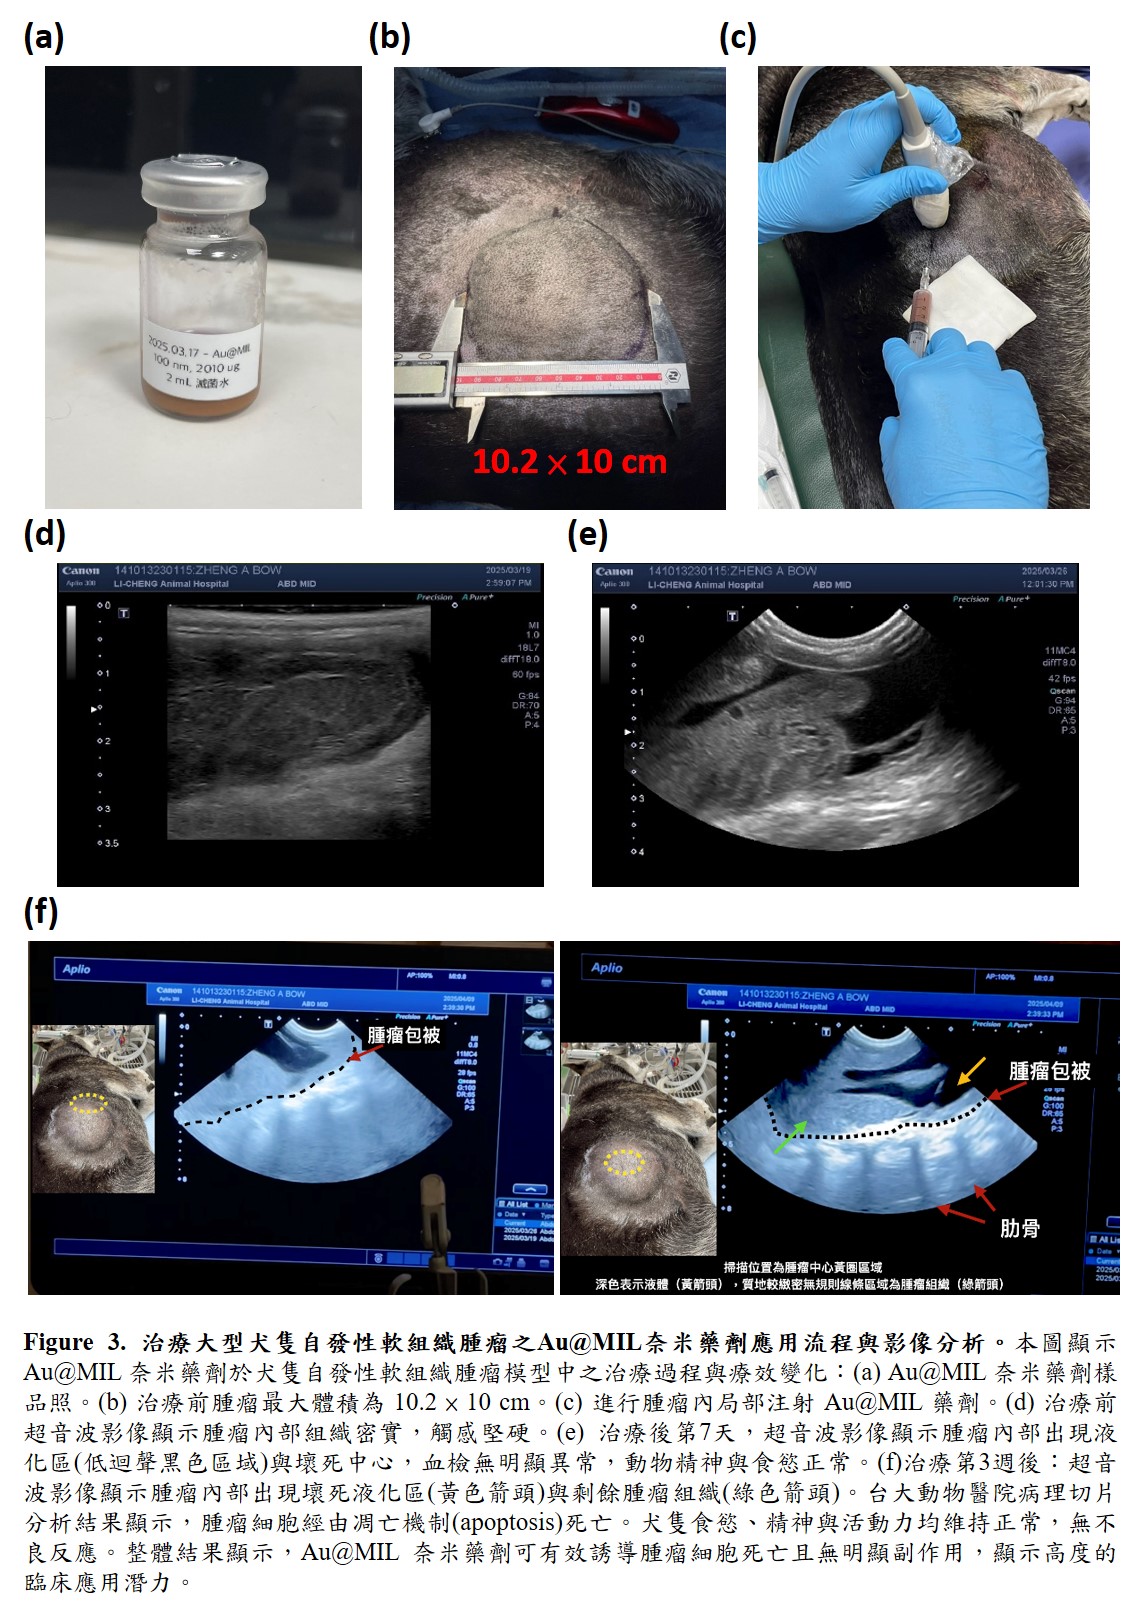

本研究開發創新癌症治療技術—電活性脂質膜金奈米複合粒子。此技術結合具胞外電子傳遞能力的電活性脂質膜與金奈米粒子,建立高效電子傳遞平台,破壞癌細胞氧化還原平衡,引發細胞凋亡,並對正常細胞無明顯毒性。小鼠與比較醫學大型犬隻實驗證實其療效與安全性,具備成為新一代精準且低副作用癌症治療策略的潛力。